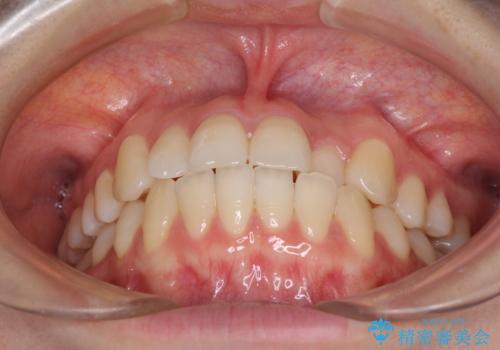

前歯のクロスバイト インビザラインによる矯正治療

- 前歯のクロスバイトを気にして来院された患者様です。

短期間での治療を希望され、ワイヤー装置とインビザラインとで悩んでいましたが、自己管理を徹底すると言うことでインビザラインによる矯正治療を行うこととしました。

しっかりとインビザラインの装着時間を守っていただいたので、1年弱で矯正治療を終えることができました。